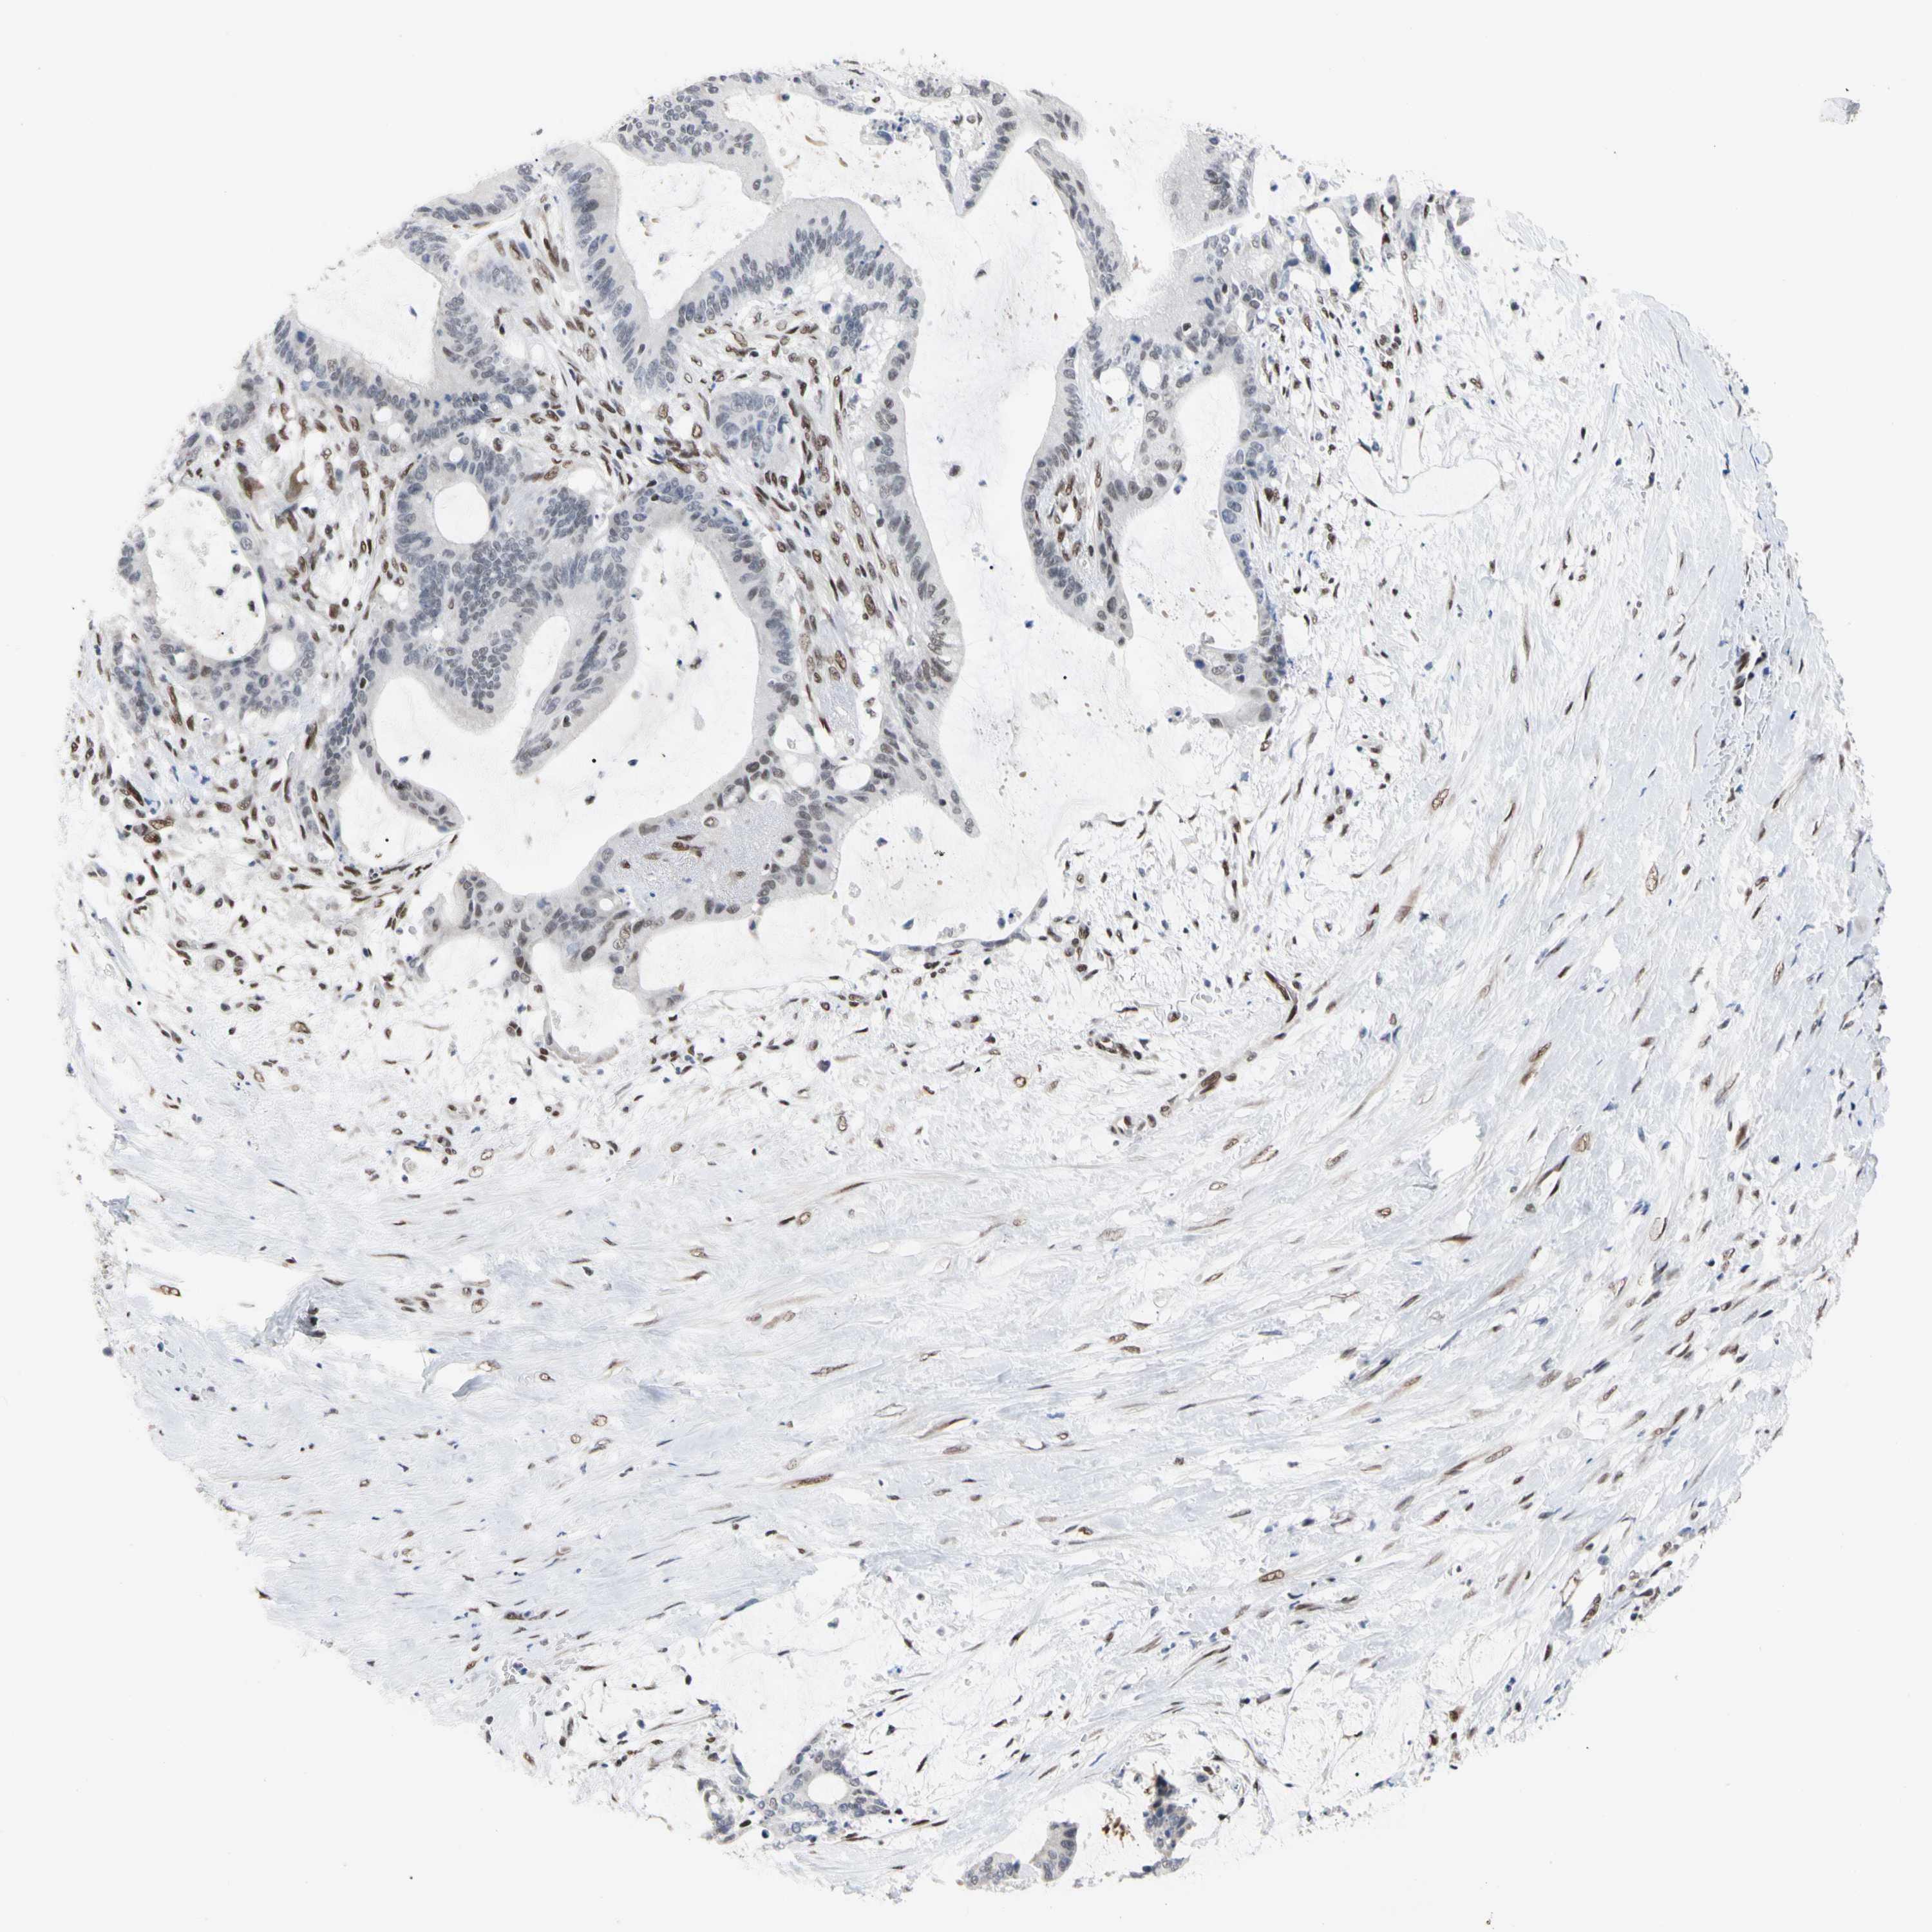

LIVER CANCER - Protein expressioni

A mouse-over function shows sample information and annotation data. Click on an image to view it in a full screen mode. Samples can be filtered based on level of antibody staining by selecting one or several of the following categories: high, medium, low and not detected. The assay and annotation is described here.

Note that samples used for immunohistochemistry by the Human Protein Atlas do not correspond to samples in the TCGA dataset.

Antibody stainingi

Antibody staining in the annotated cell types in the current human tissue is reported as not detected, low, medium, or high, based on conventional immunohistochemistry profiling in selected tissues. This score is based on the combination of the staining intensity and fraction of stained cells.

Each image is clickable and will lead to virtual microscopy that enables deeper exploration of all samples and also displays staining intensity scores, fraction scores and subcellular localization as well as patient and tissue information for each sample.

Antibody HPA008320

Antibody HPA008502

Staining

High

Medium

Low

Not detected

Intensity

Strong

Moderate

Weak

Negative

Quantity

>75%

75%-25%

<25%

None

Location

Nuclear

Cytoplasmic/membranous

Cytoplasmic/membranous,nuclear

Cholangiocarcinoma

Carcinoma, Hepatocellular, NOS